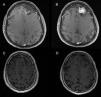

Patients and methodsSix patients with cystic meningiomas were included in the study. All patients underwent a cranial computed tomography scan and magnetic resonance imaging (MRI) evaluation, pre- and postoperatively.

ResultsAll patients presented with long standing headache dating back at least two years. There was no gender predominance in our series. Radiological evaluation revealed two parasagittal and two convexity meningiomas located at the frontal region. Two lesions were located at the tuberculum sellae and the foramen magnum. All of the tumors were totally excised (Simpson Grade I or II). Pathology results included meningothelial meningioma in three patients, angiomatous meningioma in two patients, and metaplastic meningioma in one patient. In two patients, the cystic meningiomas were resected with the use of sodium fluorescein (Na-Fl) under a YELLOW 560nm microscope filter. Na-Fl was found to be very useful in demonstrating the brain–tumor interface, and it was especially effective in resecting the cyst wall of the peritumoural cystic meningiomas. None of the patients had any complications, and no recurrences were noted in any of the patients within the mean follow-up period of 51 months (range: 16–102 months).